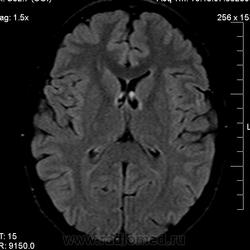

Можно ли  трактовать участок повышенного МР-сигнала по Т2 в правой лобной доле как участок перивентрикулярного глиоза?

1) господа МРТшники, если это расширенное вирхов-робиновское пространство, как вы объясните тот факт, что в TIRM последовательности сигнал от данного участка высокий?

Большое спасибо. Да, симметричная линейная паравентрикулярная структура в области передних рогов встречается часто, на что обычно не обращаю внимания. В этом случае смутила ее асимметричность (особенно на Coг. срезах), если думать что это Вирхова-Робина, то возможно это слабо выраженный периваскулярный глиоз.